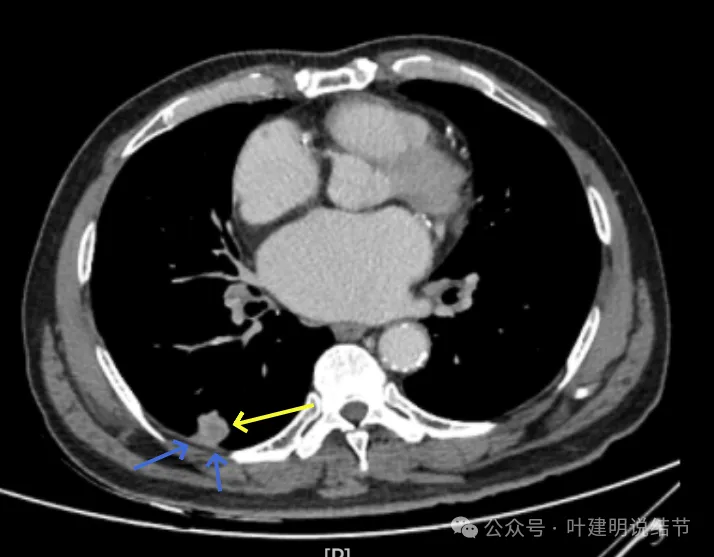

右下新增病灶,混合密度,整体轮廓较清,瘤肺边界欠清。

有小血管进入,边缘毛糙。

局部有毛刺,但不够锐利;病灶感觉有一层晕似的,邻近胸膜下也有淡磨玻璃影。

实性密度为主,周围少许很淡的磨玻璃影。

边缘不平有毛刺,但不锐利;贴着胸膜但无明显牵拉。局部表面有浅分叶似的,但总体膨胀感不够。

病灶表面不光滑,边上有晕,邻近有淡磨,贴着胸膜无牵拉。

病灶边缘欠清晰,瘤肺边界稍模糊。较宽的基底贴着胸膜。

病灶有血管进入,有浅分叶,实性为主,邻近胸膜有片状淡磨玻璃影,近胸膜无牵拉。但有一定膨胀性。

病灶实性,与血管关系较为密切。

血管走向病灶,但似乎没有被病灶影响,有向内侧的分支甚至没有哪怕一点凹向病灶侧。整体显得偏模糊。

边缘区域杂乱,边糊。

增强纵隔窗见病灶内部的密度好像低于周围区域,像坏死。

邻近胸膜无牵拉,灶内有低密度区,局部有点状液性密度。邻近胸膜较为广泛的增厚或胸膜反应。

病灶与胸膜接触面宽,病灶内部密度较低。